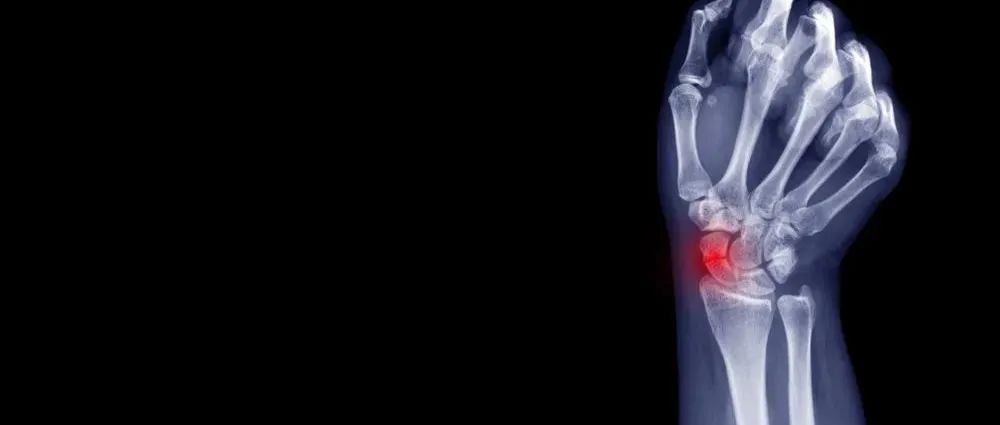

本文未经授权禁止转载桡骨远端骨折是指距桡骨远端关节面3cm以内的骨折,是临床上最常见的骨折之一,约占急诊骨折病人的1/6。直接暴力和间接暴力均可造成桡骨远端骨折,但多为间接暴力所致。主要发生在6-10岁和60-75岁两个年龄阶段。 分型对桡骨远端骨折分型的理解,有助于正确的治疗。(图2-1)图2-1 桡骨远端骨折AO分型桡骨远端骨折,若有移位,意味着一侧的深筋膜撕裂,失去了“软组织夹板”的作用。(图2-2,图2-3)...

腕舟骨骨折是腕骨中最常见的骨折,也是上肢最容易出现坏死和骨不连的骨折,本文为大家详细整理了腕舟骨骨折的诊治技巧,另附详细手术步骤,供大家参考!本文作者:舟骨骨折的临床解剖舟骨位于近排腕骨的桡侧,是小而不规则的 S 型管状骨,完全位于腕关节内,与腕的长轴和水平轴均成 45° 的平面。图源:《奈特骨科疾病彩色图谱》舟骨 80% 以上的表面是关节软骨面,起着腕中关节的「桥梁」作用,连接并同步近远排腕骨的活动。...